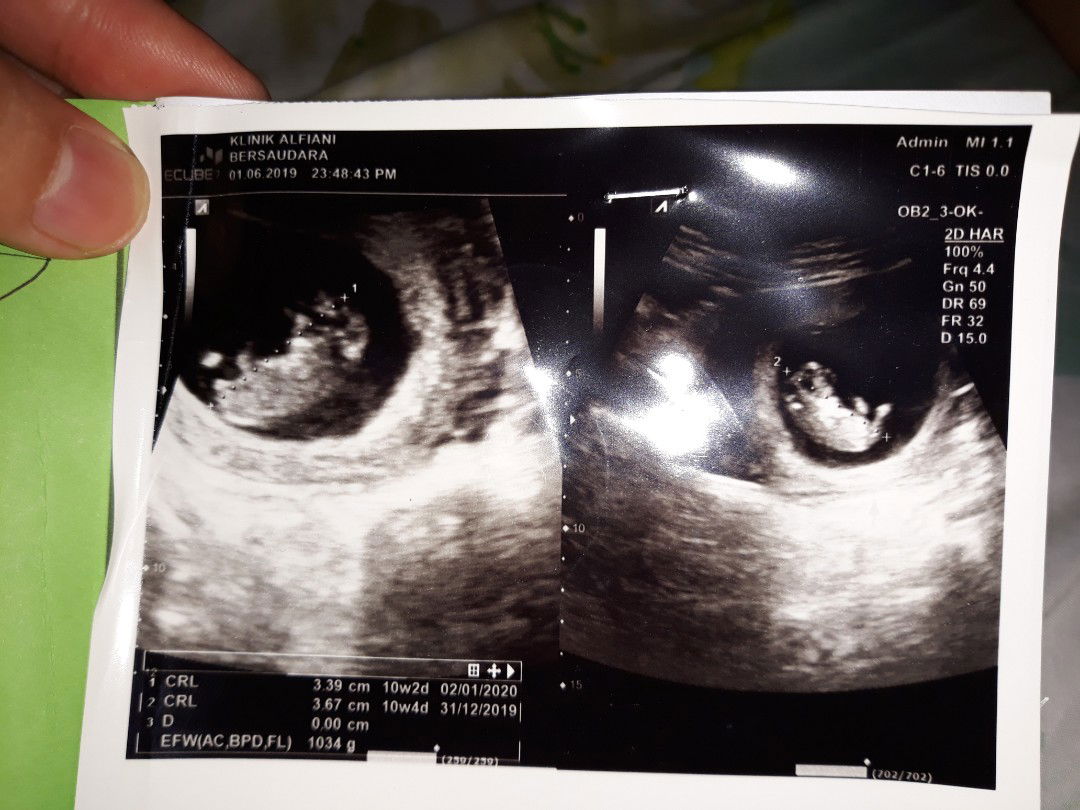

Hasil USG

Bund ada yg tau ngk hasil USG ku kemaren mana ya yg menunjukkn berat janinnya? Aku hamil 10w4d